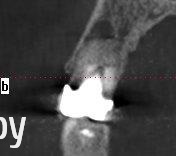

Таня-К Опубликовано 21 июня, 2014 Поделиться Опубликовано 21 июня, 2014 Уважаемые врачи, помогите, пожалуста, с выбором метода лечения 15 зуба.В разных клиниках предложены такие решения:1. Снятие коронки, удаление штифтовой конструкции, ревизия двоканального зуба,озонирование каналов перед пломбированием, пломба, временная коронка, постоянная коронка.2. Резекция верхушки корня с ретроградным пломбированием, костная пластика альвеолярного отростка.3. Удаление и имплантация.Какой метод лечения Вы считаете оптимальным с медицинской точки зрения?Большое спасибо всем. Ссылка на комментарий